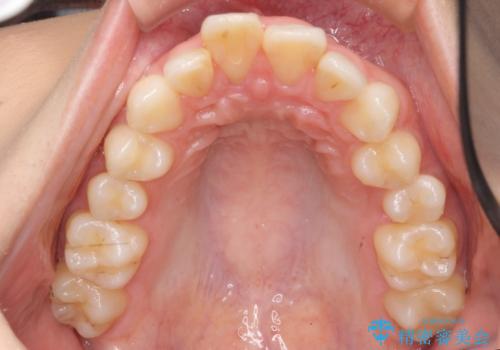

出っ歯 下の歯のガタガタ 下の前歯のみ1本抜歯 マウスピースで1年

下の前歯のがたつきがひどく、非抜歯では難しい状態でした。

古典的な方法では4本抜歯した後、ワイヤー矯正という方法も選択肢には上がりましたが、下の前歯を1本だけ抜くことにし、マウスピースで短期間で治療を終わらせるようにしました。

治療も比較的短期間で終わり、大変喜んでいただきました。

下の前歯を1本抜くと上下の正中はあいませんが、ほとんど目立ちません。